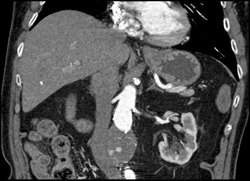

Pancreatic Mass With Incidental Endoleak